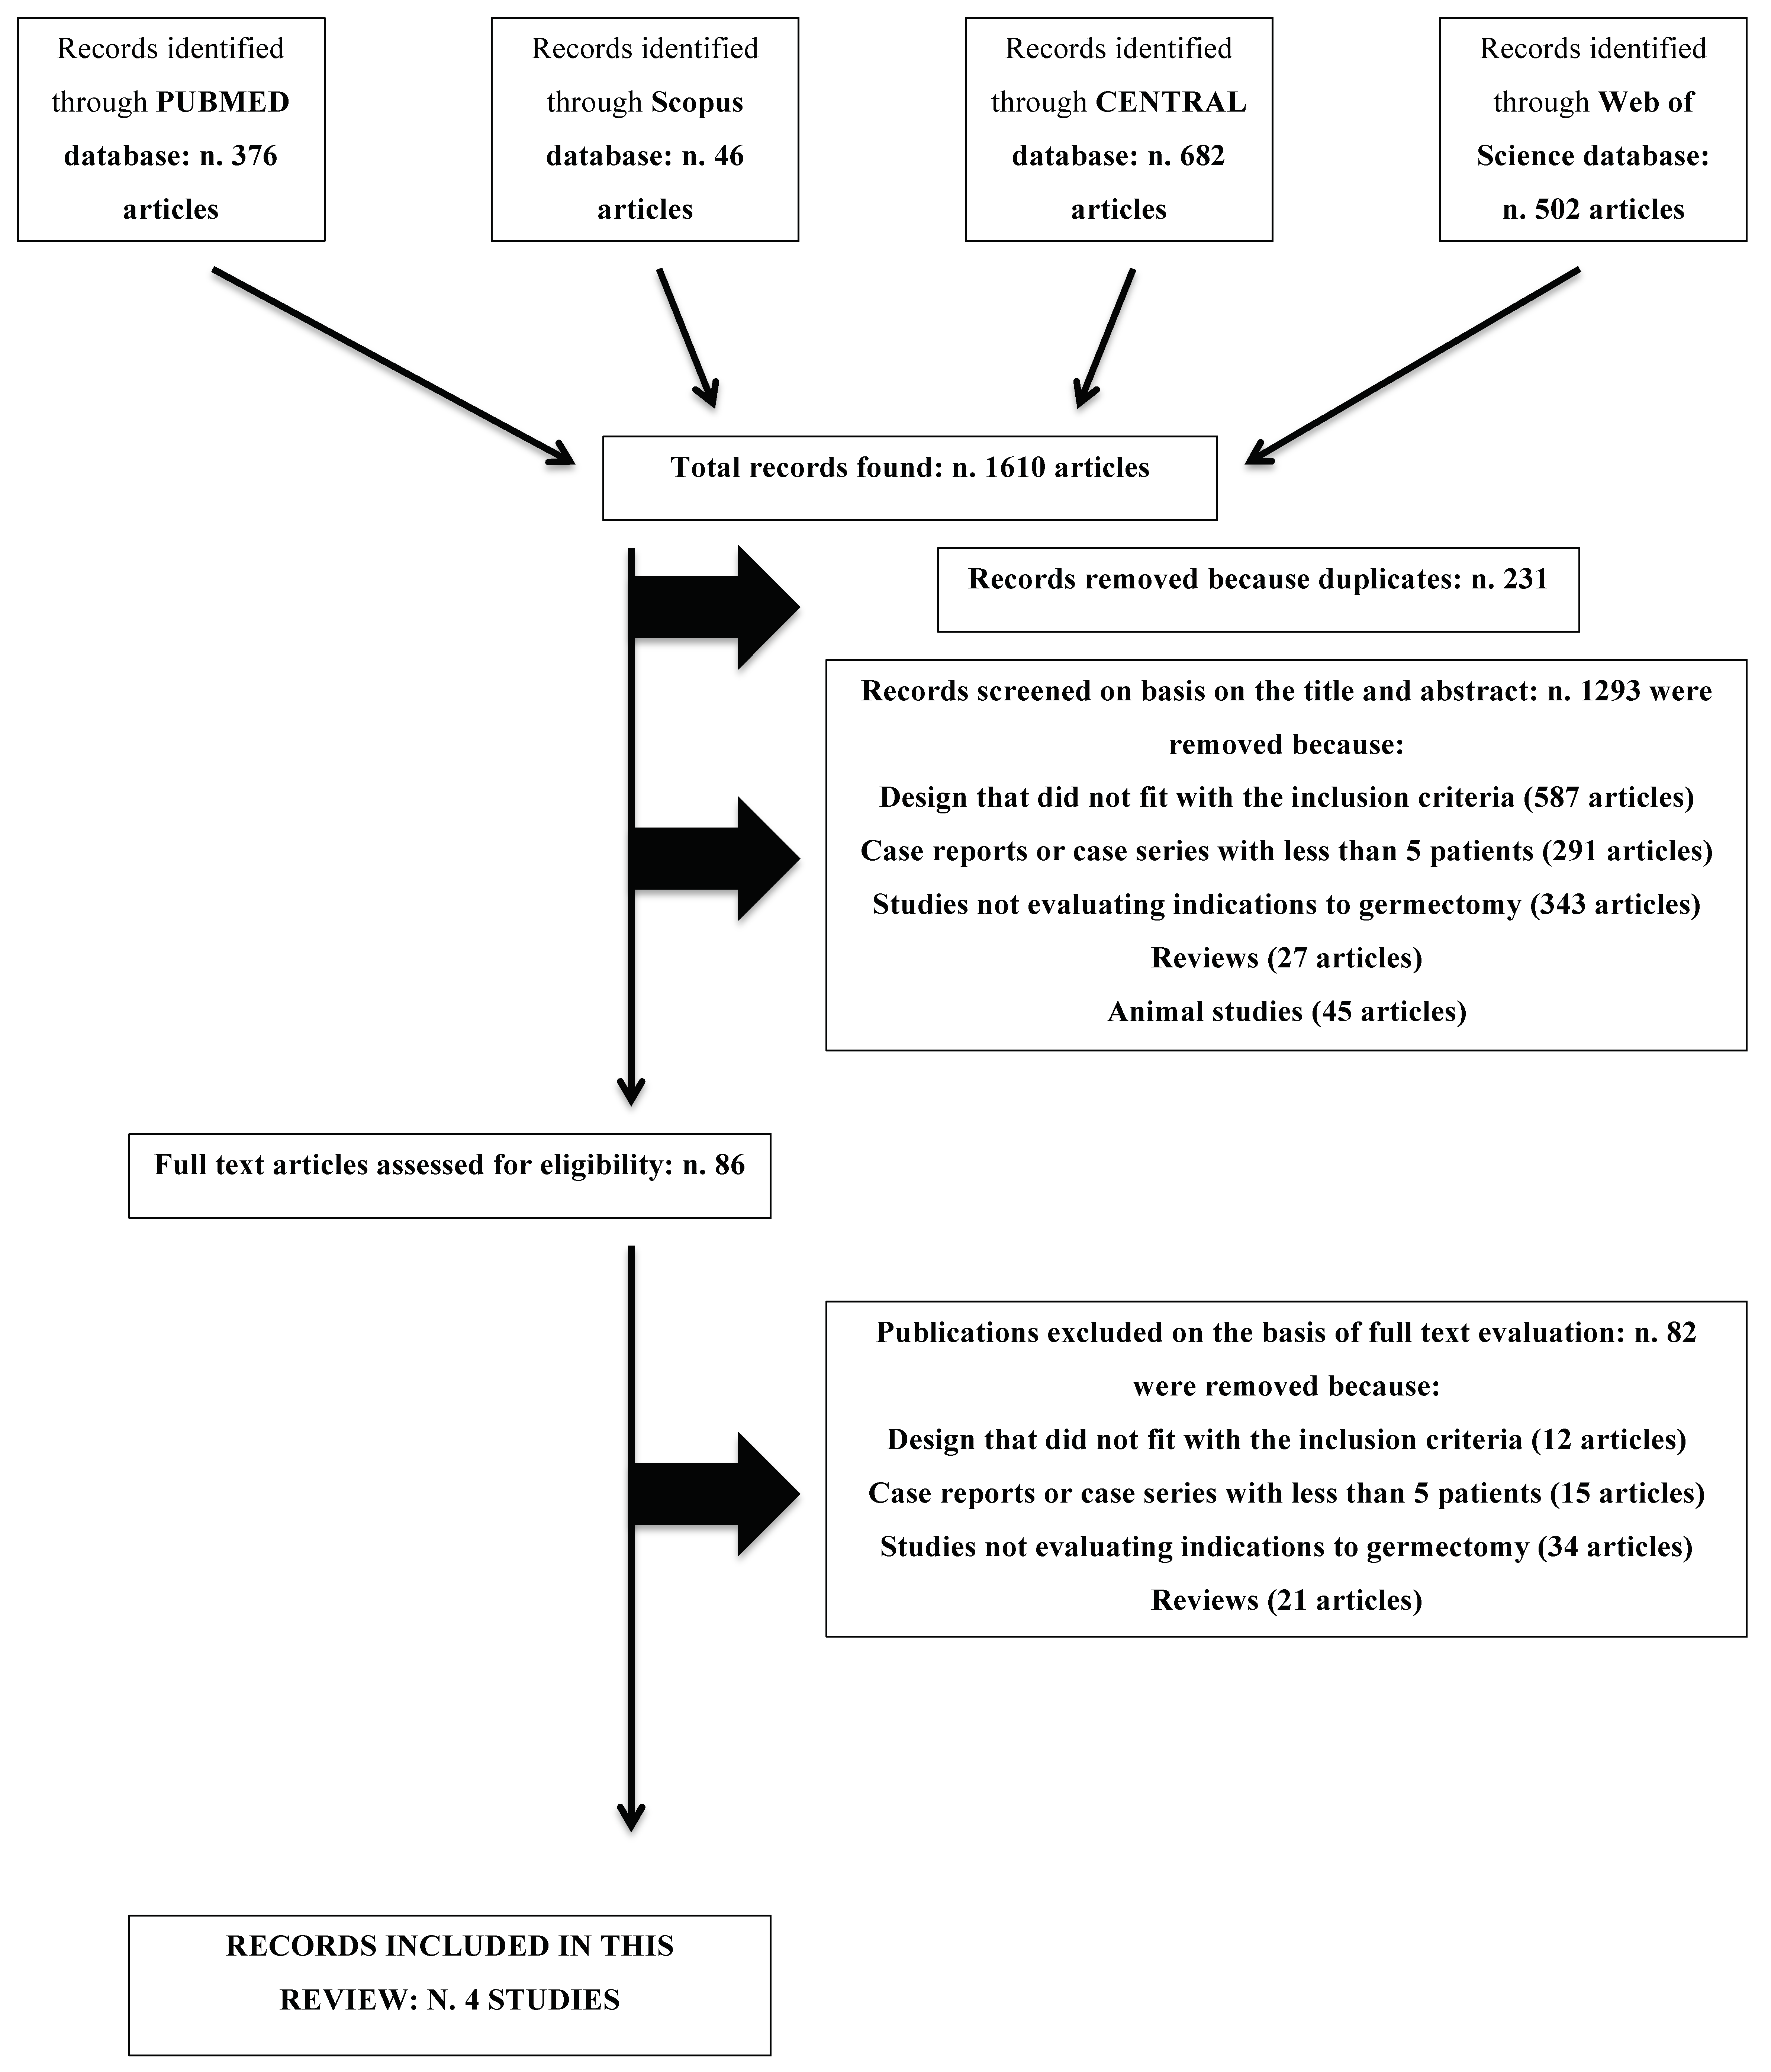

2.4. Study Selection

3.1. Exclusion of Studies